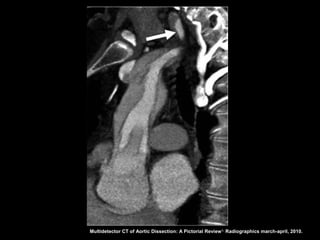

Dissecção aórtica

Angiotomografia

Diagnóstico: identificação do flap intimal, que se

apresenta como uma fina membrana separando a

luz falsa da verdadeira;

Sensibilidade e especifidade acima de 95% na

detecção do flap intimal;

Após diagnóstico: localizar, definir envolvimento de

ramos aórticos e identificar fatores agravantes

relacionados à própria aorta.

Multidetector CT of Aortic Dissection: A Pictorial Review 1. Radiographics march-april, 2010.